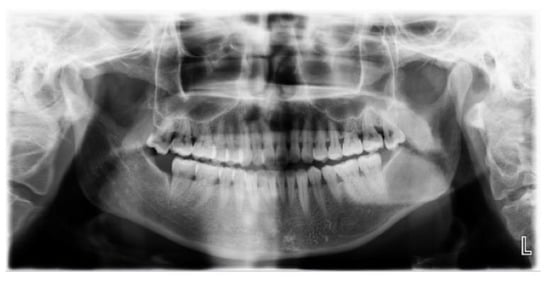

2.2. Case 2